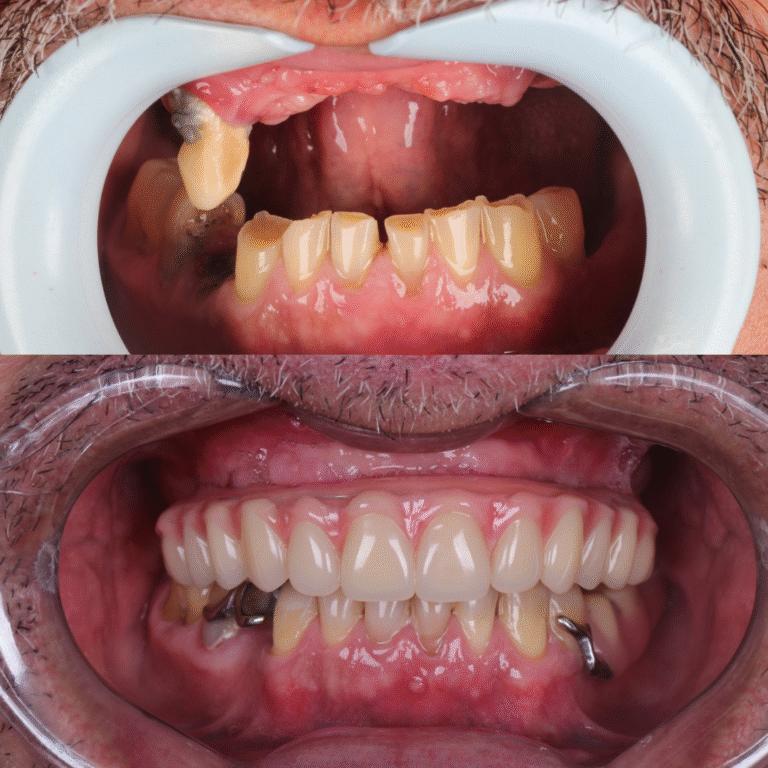

O All-on-Four é um protocolo de implantes dentários que utiliza apenas 4 implantes para fixar uma prótese total, substituindo todos os dentes da arcada.

Diferente de técnicas convencionais, não exige enxertos ósseos na maioria dos casos, tornando o tratamento mais rápido e confortável.

Perderam todos os dentes ou têm dentes comprometidos e desejam uma solução fixa e duradoura.

Buscam recuperar a função mastigatória para voltar a se alimentar com liberdade e prazer.

Em muitos casos, é possível instalar dentes fixos no mesmo dia da cirurgia. Isso significa que o paciente recupera a estética do sorriso e a função mastigatória muito mais rápido do que em técnicas convencionais.

Segundo o Dr. Arnaldo, pioneiro em Belém na técnica do All-on-Four, o tratamento com implantes, especialmente a prótese protocolo, vai muito além da cirurgia.

Planejamento minucioso, cada caso é estudado em detalhe, respeitando as necessidades e particularidades de cada paciente.

Execução precisa, técnicas avançadas e seguras garantem conforto durante o procedimento e resultados previsíveis.